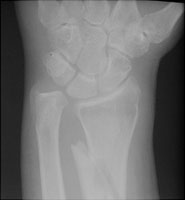

The Barton fracture consists of an intraarticular fracture of the dorsal margin of the distal radius. The fracture line is oblique and extends to the radiocarpal joint. The fracture results from a fall on an outstretched hand.

- Click on the image for a larger versionCOblique radiograph of the wrist. This shows the fracture of the dorsal margin of the distal radius with some distraction between the major fracture fragments.